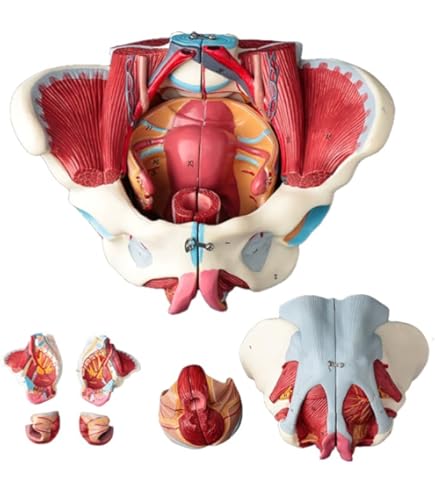

KIYOMARU 骨盤底筋付き女性骨盤模型 人体模型 8パーツ KIYOMARU 骨盤底筋付き女性骨盤模型 人体模型 8パーツ - メルカリの詳細情報

KIYOMARU 骨盤底筋付き女性骨盤模型 人体模型 8パーツ - メルカリ。Amazon.co.jp: 人体モデル 女性骨盤モデル 骨盤底筋ベル 1:1。Amazon.co.jp: 骨盤靭帯や骨盤底筋,骨盤内臓,血管や神経なども。【新品・未開封品】【即日発送】『KIYOMARU 骨盤底筋付き女性骨盤模型 人体模型 8パーツ 理学療法士監修 生殖器 膀胱 直腸 坐骨神経・陰部神経 日本語説明書付き 』参考価格:13980円 ✅解剖の理解や臨床のサポート:骨盤底筋や一部の神経(坐骨神経、陰部神経)、生殖器や排泄器が再現されており、解剖の理解や臨床をサポートしてくれます(日本語説明書付き)✅分解&組立可能:骨盤本体(骨盤底筋、一部の神経付き)、膀胱、子宮、直腸、会陰部、仙結節靭帯にて分解可能。✅サイズ(土台あり):幅26cm×奥行17cm×高さ24cm (骨盤腔の直径 左右約11.5cm 前後11cm) 重量 約1400g 原産国:中国。Amazon.co.jp: 人体モデル 女性骨盤モデル 骨盤底筋ベル 1:1。説明・セミナー・実技トレーニングなど幅広い用途でご使用いただけます✅各分野の教材として:産婦人科・泌尿器科・整形外科・リハビリ・ヨガ・整体など各方面にて説明や学習の理解の促進に。可動式脊椎模型 約90cm 椎間板突出(ヘルニア)モデル スタンド付き